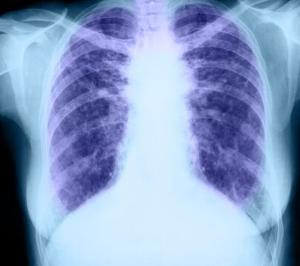

过度通气综合征(hyperventilation syndrome)是由于通气过度超过生理代谢需要而引起的一组症候群。本征所指的是没有器质性病变的任何原因,而发作时有呼吸运动加快,产生动脉血二氧化碳分压降低(低于5kPa),呼吸性碱中毒,并有交感神经系统兴奋,临床上表现各种各样症状。所有症状都可以用过度通气和呼吸性碱中毒来解释,症状的发生与呼吸控制系统异常、自主呼吸调节丧失了稳定性(很可能是脑干以上的高位神经结构,如下丘脑)有关。过度通气综合征的概念包括以下3个含义:①有躯体症状;②有可以导致过度通气的呼吸调节异常;③躯体症状与呼吸调节异常之间存在因果联系,也就是说躯体症状是由呼吸调节异常引起的。[1]